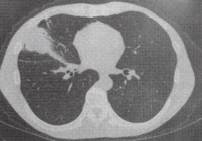

(2)肺转移瘤结节边缘光整,部分病灶融合,出现分叶征。常难与肺癌鉴别,其转移 瘤可能性与原发肿瘤组织类型和患者年龄密切相关,常见原发肿瘤包括黑色素瘤、肉瘤、结肠癌、乳腺癌、肝癌、肾癌、膀胱癌和睾丸癌等(图3)。诊断主要依靠原发恶性肿瘤病史。 医学百科网 | YxBaike.Com